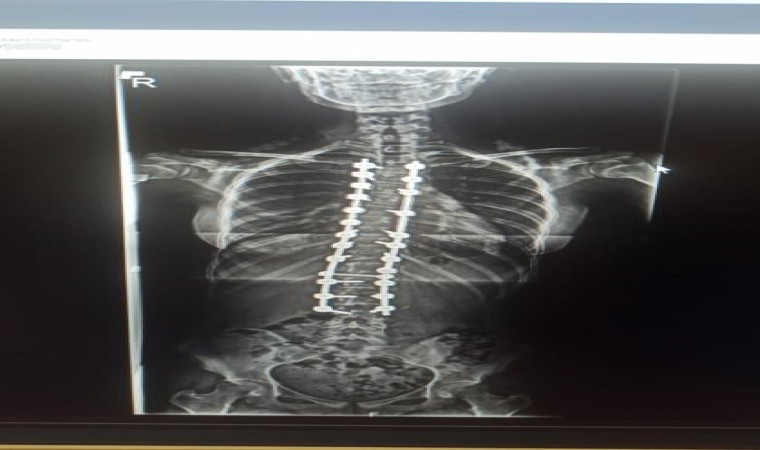

Samsun’da yaşayan ve bir süredir skolyoz hastası olan 10’uncu sınıf öğrencisi Zeynep Pehlivan, tedavi için Antalya Memorial Hastanesi Ortopedi ve Travmatoloji Bölümünden Doç. Dr. Ömer Bozduman’a ulaştı. Yapılan görüşmelerin ardından Pehlivan ve ailesi Antalya’ya davet edildi. 4 gün önce Antalya’ya gelen Zeynep Pehlivan için ameliyat kararı alındı. Ameliyatla genç kızın sırtında ve belinde bulunan eğrilikler enstrümantasyonlu bir sistemle füzyon cerrahi tedavisi yaparak düzeltildi. Ameliyatın hemen ardından bir gün sonra yürümeye başlayan Pehlivan, 4 gün sonra taburcu edildi.

Zeynep’in skolyoz hastalığından dolayı uzun zamandır takiplerinde olduğunu belirten Doç. Dr. Ömer Bozduman, “Rahatsızlığı gerilemek yerine ilerleme olunca müdahale etmeye karar verdik. Ameliyatını gerçekleştirdik. Sırtında ve belinde olan eğriliklerini enstrümantasyonlu bir sistemle füzyon cerrahi tedavisi yaparak düzelttik. Ameliyattan sonra birinci gün yürüttük. Problem yaşamadık, dördüncü gün taburcu edeceğiz. Zeynep’in en sık hareketlenmelerinin olduğu boyun sırt bileşkesine beliyle kalça bileşkesine dokunmadık. Daha az hareketsiz olan sırt bölgesine füzyon cerrahi yaptık. Bundan sonra çok fazla bir fonksiyon kaybı olacağını düşünmüyoruz” dedi.